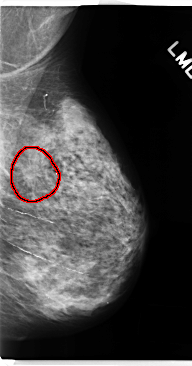

C_0158_1.LEFT_MLO

LEFT_MLO LINES 4752 PIXELS_PER_LINE 2488 BITS_PER_PIXEL 12 RESOLUTION 50 OVERLAY

FILE: C_0158_1.LEFT_MLO.OVERLAY

TOTAL_ABNORMALITIES 1

ABNORMALITY 1

LESION_TYPE MASS SHAPE IRREGULAR MARGINS SPICULATED

ASSESSMENT 5

SUBTLETY 4

PATHOLOGY MALIGNANT

TOTAL_OUTLINES 1

BOUNDARY